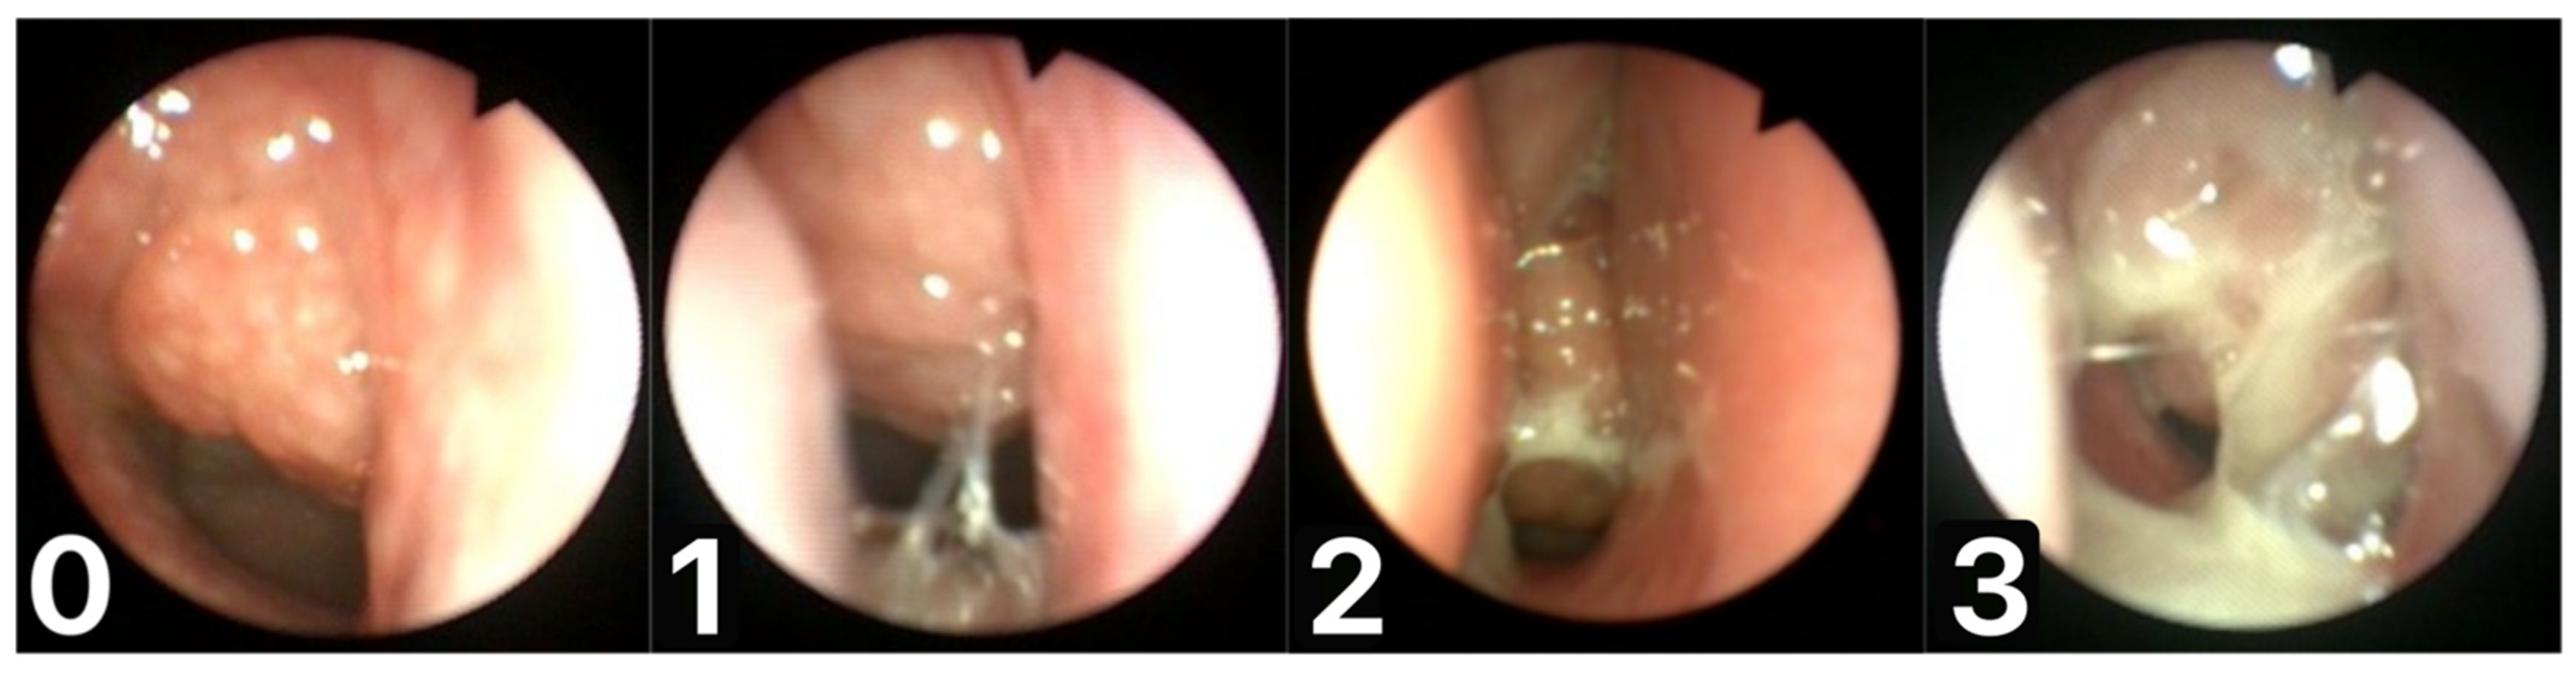

| Summer adenoid mucus coverage (MASNA scale) | 0 | 47 (22.93%) |

| 1 | 82 (40.00%) | |

| 2 | 53 (25.85%) | |

| 3 | 23 (11.22%) | |

| Winter adenoid mucus coverage (MASNA scale) | 0 | 25 (12.20%) |

| 1 | 67 (32.68%) | |

| 2 | 65 (31.71%) | |

| 3 | 48 (23.41%) | |